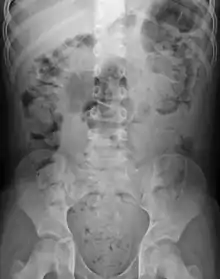

Abdominal X-rays are generally only performed if bowel obstruction is suspected, may reveal extensive impacted fecal matter in the colon, and may confirm or rule out other causes of similar symptoms.[24][16]